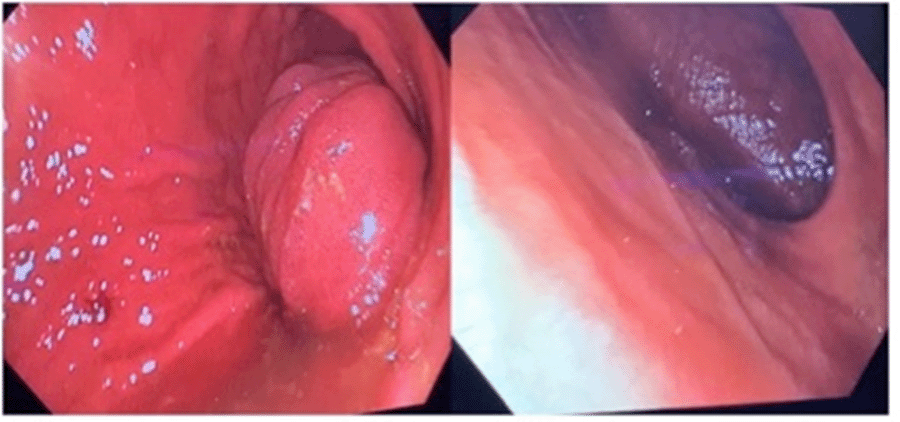

Since the patient was stable, consent was obtained for an initial upper endoscopy to further define and clarify anatomy, followed by laparotomy immediately thereafter. The operating surgeon had full anesthesia capabilities and performed the endoscopy in our surgical endoscopy unit. Upon passage of the scope into the distal gastric body, an intussuscepting limb of the small bowel was encountered, which was fully viable. Its origin was not initially apparent, and the scope could be maneuvered through the patient’s native pylorus into a large blind pouch of proximal duodenum with no outlet. There was no bile in the stomach or this blind ending pouch (Figure 3). A laparotomy followed, and examination of the abdominal content revealed the colon to indeed be on the left side of the abdomen. The appendix was surgically absent, consistent with prior Ladd’s procedure. There was complete atresia of the second portion of the duodenum. A surgical gastrojejunostomy was noted, the efferent limb of which had intussuscepted retrograde through the gastrojejunal anastomosis into the gastric lumen. The intussusception was manually reduced by grasping the stomach at the cephalad aspect of the intussusception and pushing the jejunum within its lumen distally back toward the anastomosis while placing only minimal traction on the intussuscepted jejunal limb from below. Once fully reduced, there was no evidence of a lead point, and jejunal viability was confirmed (Figure 4).

Figure 3. Endoscopic Images. Published with Permission

Noted viable intussucepted jejunum in gastric antrum (left) and blind-ending proximal duodenal pouch (right).